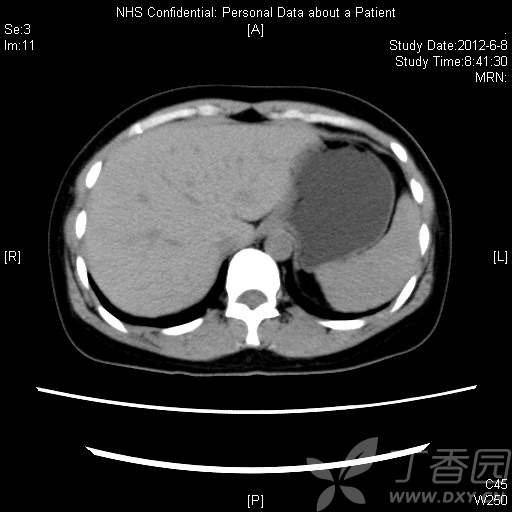

CT资料:

img